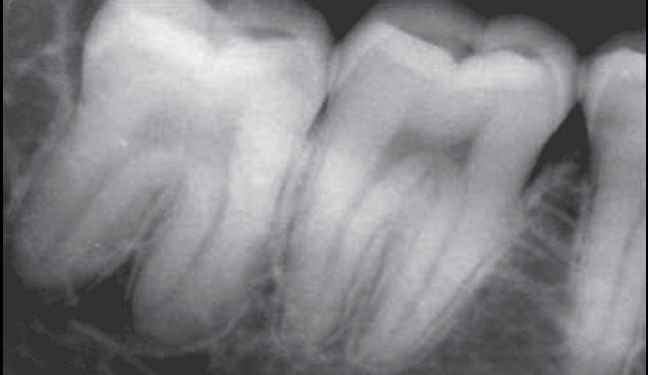

根部阻力亦可称根部骨阻力或牙根阻力,其主要根据X线片分析,阻力大小与牙位、牙根数目、牙根形态、根尖形态、根周骨组织情况有关。

牙根阻力以多根牙、根分歧过大、特长根、U形根、牙颈部倒凹大者阻力较大根尖区以近中弯曲、多向弯曲、根尖肥大者牙根阻力较大。

根周骨阻力以骨质增生和牙根有骨粘连者阻力较大,根周骨质疏松、有炎症性骨吸收者阻力较小。